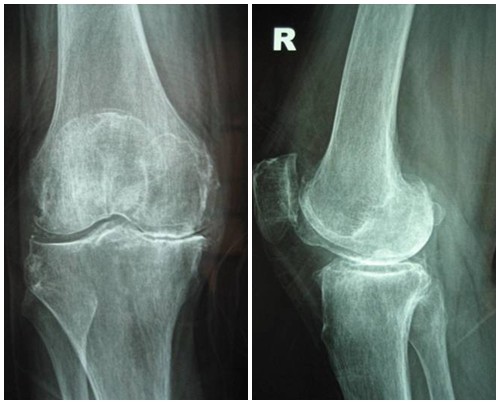

Hình ảnh của khớp gối trên phim X-quang: Khe khớp hẹp nhiều, gai xương có kích thước lớn, đặc xương dưới sụn, đầu xương biến dạng rõ.

Thoái hóa khớp gối giai đoạn 4 là giai đoạn nặng, sụn khớp bị bào mòn

Thoái hóa khớp gối đã bước vào giai đoạn nặng, sụn khớp bị bào mòn và bong tróc gần như hoàn toàn để lộ đầu xương rõ rệt. Khoảng không gian chung giữa hai đầu xương thu hẹp đáng kể, gai xương ngày càng lớn, chất nhờn bôi trơn khớp giảm nên gây ra hiện tượng ma sát giữa hai đầu xương, gây đau nhức xương khớp nghiêm trọng. Người bệnh xuất hiện một loạt các triệu chứng đau nhức liên tục, cứng khớp, khó vận động khớp, khó đi lại… ảnh hưởng đến sinh hoạt. Theo thời gian, thoái hóa khớp gối có thể gây biến dạng khớp hoàn toàn, gây lệch trục khớp…